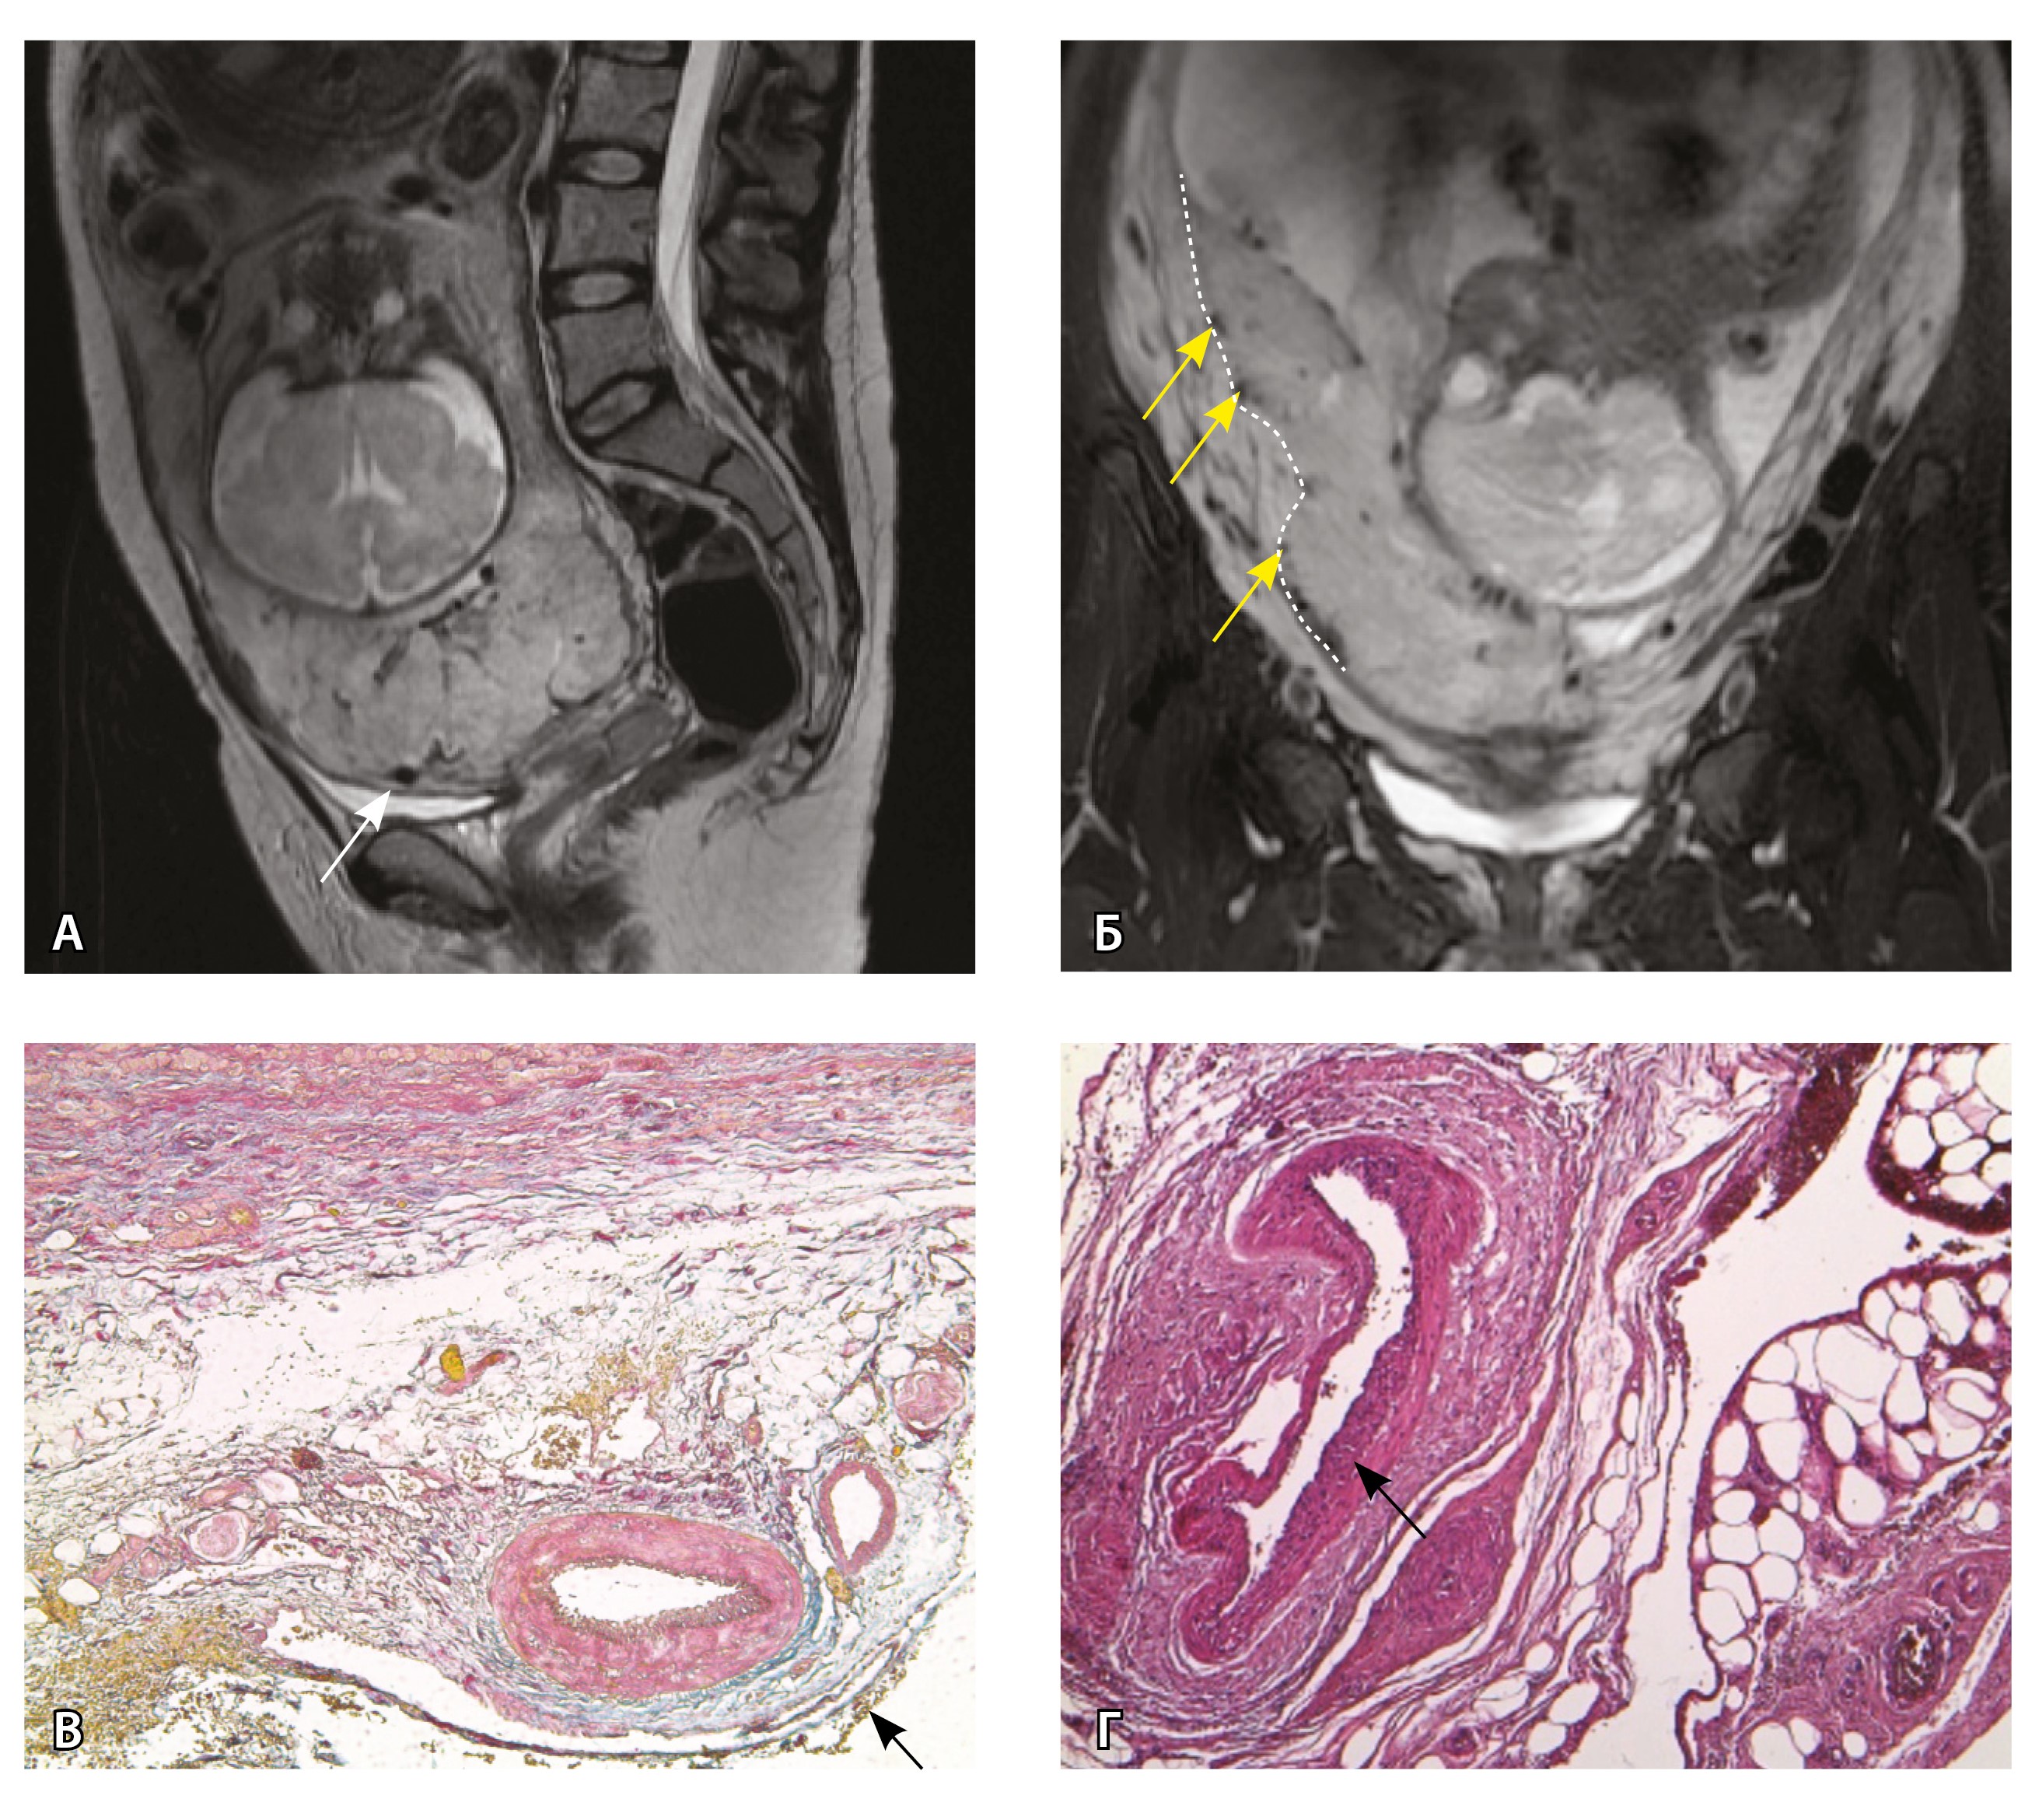

Рис. 13. Самые крупные сосуды в пределах серозной оболочки стенки матки: А, Б – серийные срезы артерии; × 50. При окраске по Маллори (А) видна тонкая полоска мезотелия (черная стрелка), слабо дифференцированная мышечная стенка артерии, вокруг нее – плотная коллагеновая оболочка (желтая стрелка), в просвете определяются тромботические массы. При окраске по Вейгерту (Б) наблюдается полная потеря внутренней и внешней эластических мембран

Анализ частоты встречаемости сосудов 4-го типа при различных степенях приращения плаценты (рис. 14) показал: при плотном прикреплении плаценты (gr 2) и поверхностном приращении (gr 3) сосуды данного типа не выявлены, при pl. increta (gr 4) частота встречаемости незначительная – 16,7%, а при глубокой инвазии плаценты (pl. percreta, gr 5) сосуды этого типа преобладают (р < 0,001, хи-квадрат Пирсона).

Рис. 14. Частота встречаемости сосудов 4-го типа при различной глубине приращения плаценты (grade МАPI-RADS)